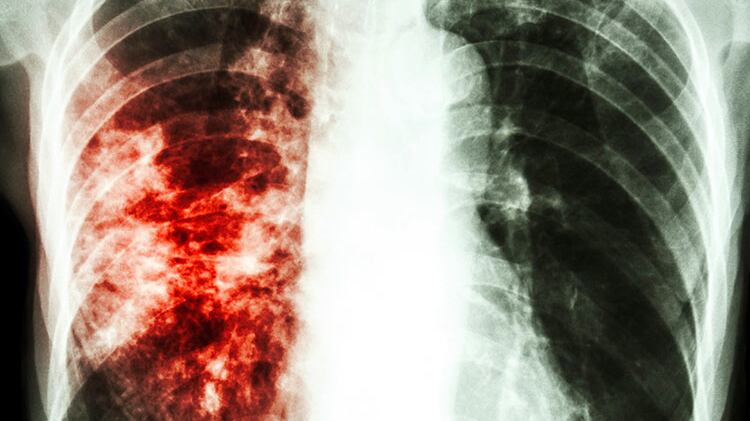

It’s not entirely clear why tuberculosis acts as some sort of COVID firewall. Robinson said one theory is that tuberculosis causes so much inflammation in the lung, the virus might have a hard time finding a way in. “Your lungs are like ‘Whoa, whoa, whoa,’ there’s already enough of a toxic environment for a virus that it inhibits it,” he said.